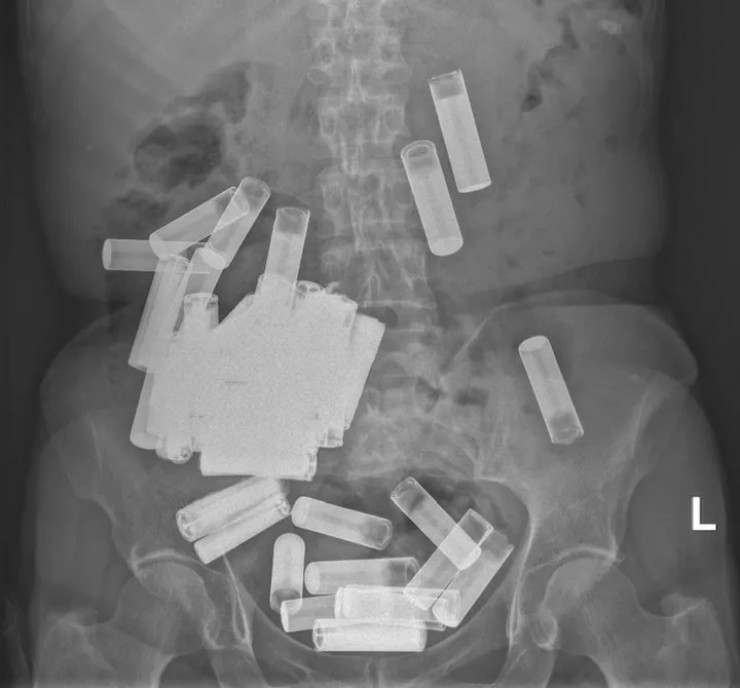

Врачи извлекли 55 батареек из желудка женщины Фото: Irish Medical Journal

В Ирландии врачи вытащили из желудка и толстой кишки 66-летней пациентки 55 пальчиковых батареек, передает Tengrinews.kz со ссылкой на HuffPost.

Жительница Дублина обратилась в госпиталь Святого Винсента с жалобами на вздутие живота и боли. Медики сделали УЗИ и обнаружили в ее желудке и толстой кишке массу посторонних предметов.

Сначала медики решили подождать, пока инородные предметы выйдут из организма естественным путем, но спустя неделю тело покинули всего пять батареек, а боль в животе пациентки усилилась. Тогда врачи решили прооперировать женщину и извлекли из нее еще 50 пальчиковых батареек.

"Насколько нам известно, этот случай представляет собой самое большое зарегистрированное количество батареек, проглоченных в один момент времени", - говорится в статье.

На данный момент пациентка находится под наблюдением врачей. О том, как такое количество батареек оказалось внутри женщины, не сообщается. Однако врачи отметили, что проглатывание батареек является весьма опасным способом членовредительства, так как может вызвать серьезные проблемы, включая повреждение слизистой оболочки, перфорацию и обструкцию.